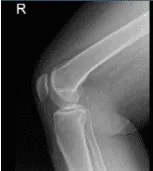

Vista lateral